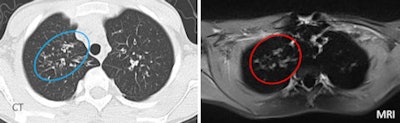

| Sometimes MRI was misleading, as in the case of a 22-year-old male patient with mild cystic fibrosis disease. Vessel depiction in MRI mimicked a large bronchiectasis of the right upper lobe. Moreover, MRI propeller sequence produced linear artifacts that derive from k-space reconstructions. The artifacts appear as lines in the lung parenchyma, creating false bronchi. All images courtesy of Dr. Perluigi Ciet. |